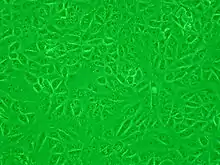

Vero (от эспер. истина) — линия клеток, используемая для культивирования[1]. Была получена из эпителия почки, взятой у африканской зеленой мартышки (Chlorocebus aethiops) 27 марта 1962 года Ясумурой и Кавакитой в университете города Тиба[2]. Культура клеток была названа эспер. vero — истина, как аббревиатура от эспер. verdo — зелёный цвет и эспер. reno — почка[3].

.jpg.webp)